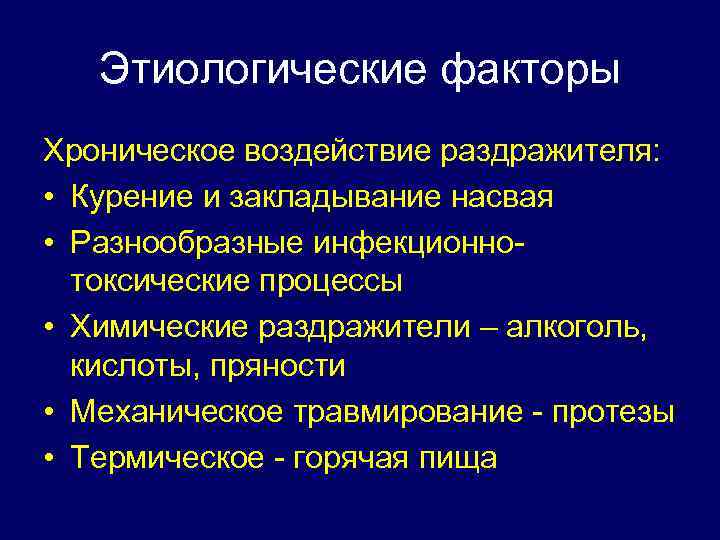

Этиологические факторы Хроническое воздействие раздражителя: • Курение и закладывание насвая • Разнообразные инфекционнотоксические процессы • Химические раздражители – алкоголь, кислоты, пряности • Механическое травмирование - протезы • Термическое - горячая пища

Этиологические факторы Хроническое воздействие раздражителя: • Курение и закладывание насвая • Разнообразные инфекционнотоксические процессы • Химические раздражители – алкоголь, кислоты, пряности • Механическое травмирование - протезы • Термическое - горячая пища